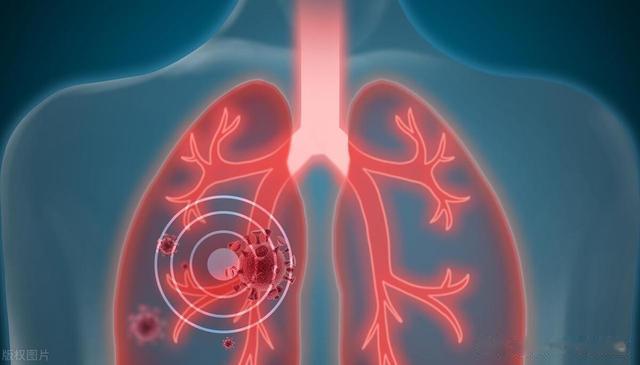

人的肺也是一样,吸烟的日子越长,烟雾里的有害物质就像黏糊糊的沥青,牢牢附着在肺泡上,让它们变得脆弱不堪。

来医院一查,肺部的CT片子上密密麻麻的阴影像是被烟熏黑的墙壁,医生的脸色严肃起来,确诊为慢性阻塞性肺病(COPD),再发展下去,很可能会进展成肺气肿甚至肺癌。

1. 肺:被“沥青”糊住的气囊烟草中的焦油、尼古丁、一氧化碳等有害物质进入肺部后,就像一层层黑色的油漆,把原本粉嫩嫩的肺泡涂成黑色,肺泡壁失去弹性,慢慢塌陷,最后形成肺气肿。

你可以想象一下,原本充满弹性的气球被反复捏扁、撑大,最终变成一块完全失去弹性的破布,呼吸就像戴着一个塑料袋,怎么吸气都不够。